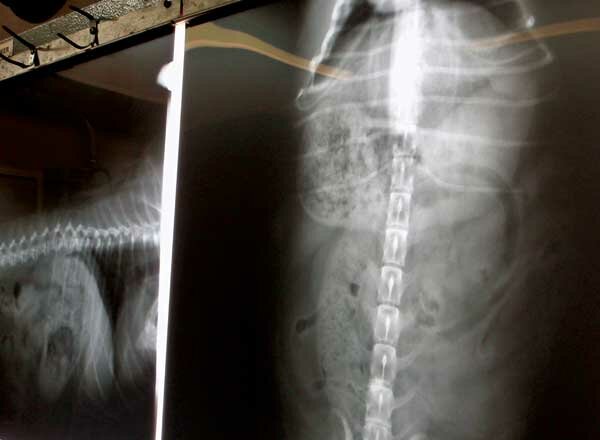

- Radiology (X-rays)